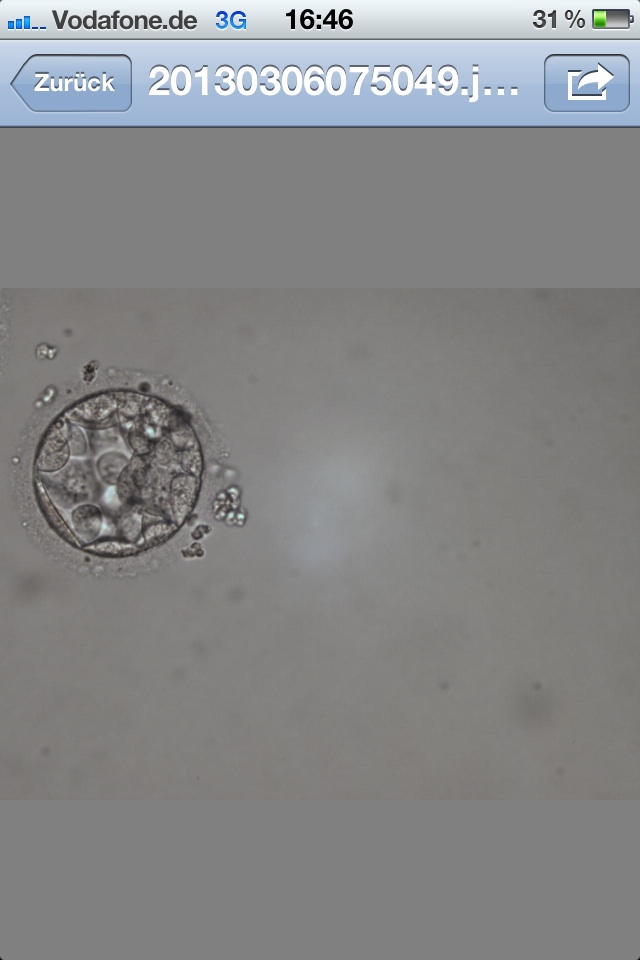

1 Bild = Blasto Tag 5